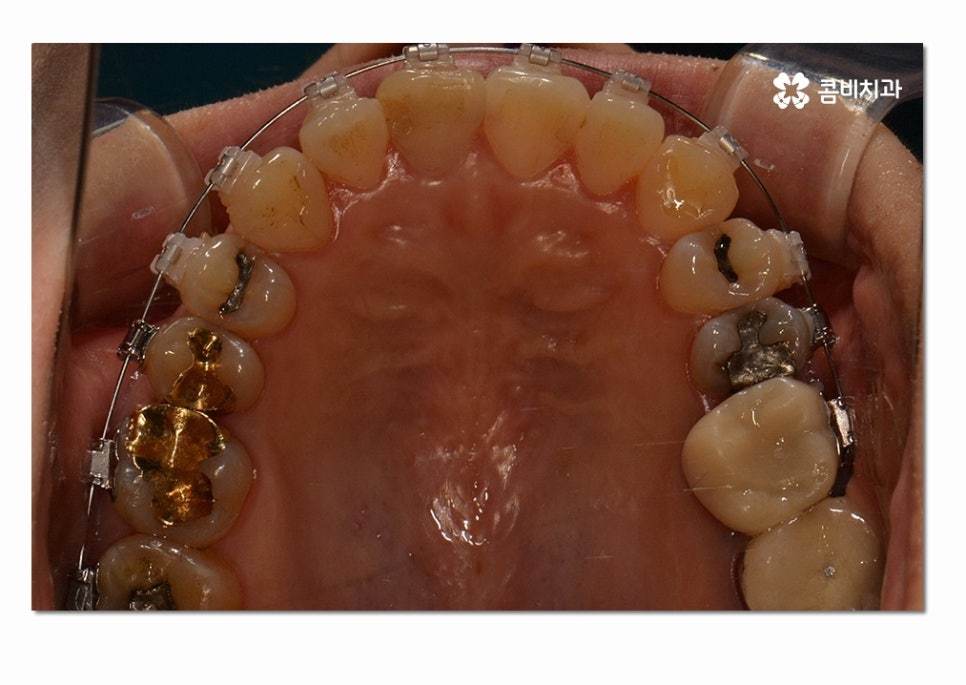

위 사례의 경우에는 3급 부정교합의 케이스로

치열이 맞지 않아 치아의 본래 기능들이 제대로 이루어지지 않고 있는 상태이며

서로 닿지 않아서 식사를 할 때마다 제대로 씹지 못하여

불편함을 느끼는 것은 물론이며 구강관리도 잘되지 않아서

충치가 많이 발생하고 있는 사례였다고 볼 수 있어요.

위 환자분의 경우에는 클리피씨 교정 장치를 통해서 치료가 진행되었으며

발치와 수술 없이 3급 부정교합을 개선한 사례라고 할 수 있어요.